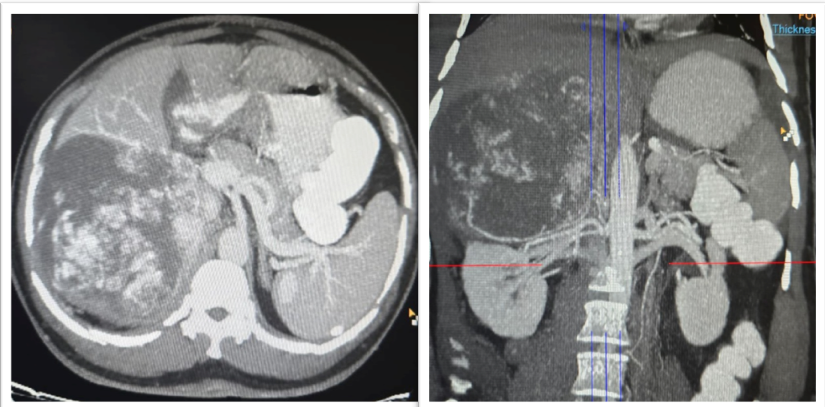

A 56-year-old man presented with a two-week history of vague, dull aching pain in the right upper abdomen. There were no accompanying constitutional symptoms such as fever, anorexia or weight loss. He was a known case of type 2 diabetes mellitus and hypertension. On general examination, he was conscious, oriented, and hemodynamically stable. Abdomen was soft, non-tender without any palpable mass. Systemic examination was unremarkable. Baseline laboratory investigations such as complete blood count, renal and liver function tests were within normal limits. Abdominal ultrasonography revealed minimal right-sided pleural effusion. Scrotal ultrasonography showed bilateral grade IV varicocele with a small right hydrocele, which was considered incidental. Contrast-enhanced computed tomography of the abdomen demonstrated a large, well-defined heterogeneously enhancing retroperitoneal mass in the right upper quadrant measuring approximately 20 × 10 cm. The lesion was inseparable from the upper pole of the right kidney and showed apparent extension into hepatic segments VI and VII, raising strong suspicion of a malignant neoplasm, most likely renal cell carcinoma with hepatic involvement (Figure 1).

Contrast-enhanced  computed  tomography  (CECT)  of  the  abdomen  showing  a  large  heterogeneously  enhancing retroperitoneal mass. (Left) Axial CT image demonstrating a well-defined heterogeneous mass in the right upper retroperitoneum, inseparable from the upper pole of the right kidney with apparent involvement of adjacent hepatic parenchyma. (Right) Coronal CT  reconstruction  showing  the  craniocaudal  extent  of  the  lesion  with  close  proximity  to  the  right  kidney  and  liver,  raising radiologic suspicion of a malignant renal neoplasm with hepatic extension.